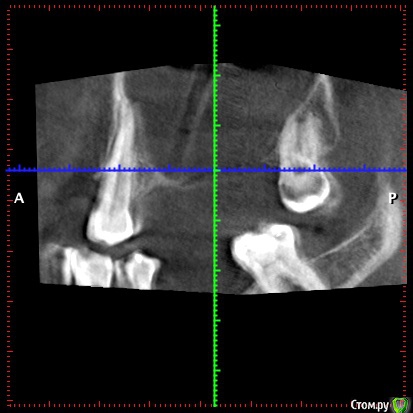

32worldwide Опубликовано 2 июня, 2020 Поделиться Опубликовано 2 июня, 2020 Вот скрины с 3Д. Там видна тень от дренирующей трубки. Вопрос такой же кто как порекомендует вести пациента дальше. И есть отправить на ЧЛХ то что там будут делать(интересно просто)? Ссылка на комментарий

АнтонТЛТ Опубликовано 2 июня, 2020 Поделиться Опубликовано 2 июня, 2020 Если отделяемого нет, то трубку можно убрать. Далее можно вести на йодоформных турундах либо просто полоскания после еды, чтобы еда туда не забивалась. Вы убрали причину (если это была одонтогенная киста), то дальше само должно заживать. Кт через 3-4 месяца для оценки динамики. Ссылка на комментарий

Irouil Опубликовано 3 июня, 2020 Поделиться Опубликовано 3 июня, 2020 (изменено) Получается дефекта стенки пазухи нет? Изменено 3 июня, 2020 пользователем Irouil Ссылка на комментарий

32worldwide Опубликовано 5 июня, 2020 Поделиться Опубликовано 5 июня, 2020 Получается дефекта стенки пазухи нет?Получается что нет. Ссылка на комментарий

32worldwide Опубликовано 5 июня, 2020 Поделиться Опубликовано 5 июня, 2020 Если отделяемого нет, то трубку можно убрать. Далее можно вести на йодоформных турундах либо просто полоскания после еды, чтобы еда туда не забивалась. Вы убрали причину (если это была одонтогенная киста), то дальше само должно заживать. Кт через 3-4 месяца для оценки динамики.Может стоит сдедать биопсию? Как вы считаете есть ли с этом кейсе что то указывающее на окнологию? По моему нет, интересно мнение коллег. Почему именно 4 месяца, обычно первый контроль заживления очага через пол года.. Ссылка на комментарий

АнтонТЛТ Опубликовано 5 июня, 2020 Поделиться Опубликовано 5 июня, 2020 Вы же зуб удаляли, у Вас больше информации. Если что-то смущает сделайте биопсию). По снимку больше на одонтогенный очаг похоже.Через 3-4 месяца уже будут видны первые изменения. Ссылка на комментарий

Irouil Опубликовано 5 июня, 2020 Поделиться Опубликовано 5 июня, 2020 Я не уверен, что тут уже что-то вырастет. Вестибулярной стенки нет, протяжённость медио-дистально большая. Если с острой стадией покончили возможно имеет смысл идти на вылущивание и потом планировать реконструкцию Ссылка на комментарий